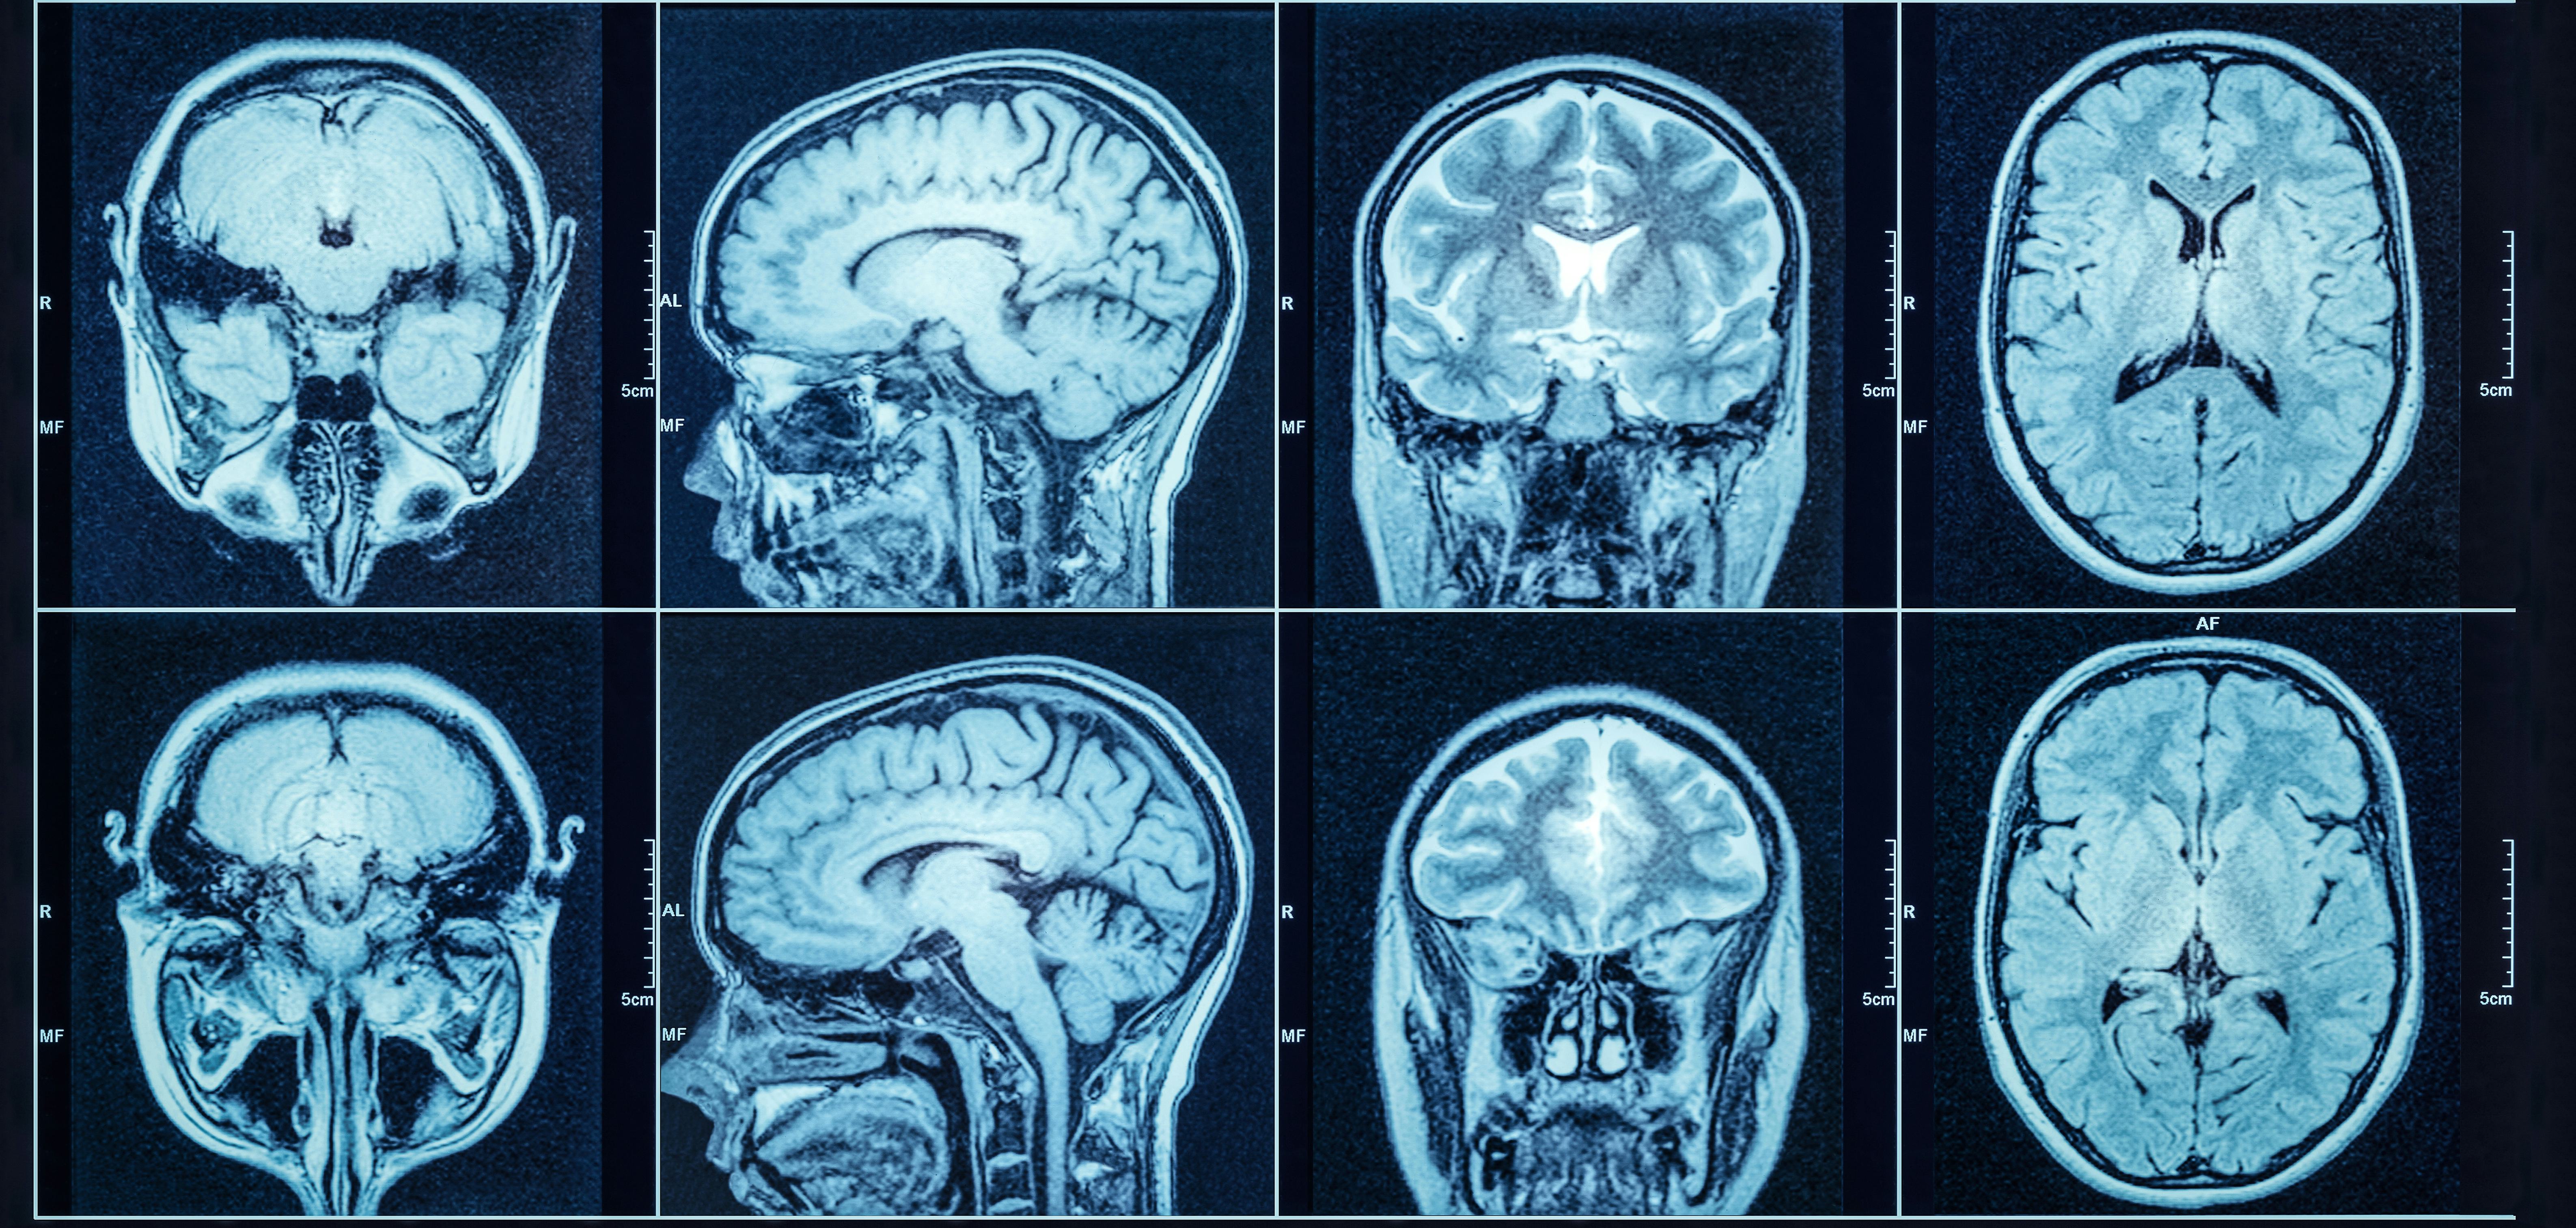

In hopes of better understanding ketamine’s Point A to Point B journey, Varley and his colleagues analyzed differences in the brains of macaques when they were on propofol compared to ketamine.

The researchers used data taken from electrical recording devices placed on the brains of macaques while anesthetized with the two drugs. The results were published in June in Royal Society Open Science.

When they plotted the brain activity on a graph, the researchers found that ketamine-induced brain activity was just that — right between wakefulness and anesthesia-induced sleep.

Varley and his colleagues’ findings make sense with what we know about what’s happening in the brain during “k-holes” or disassociative states induced by the drug. A June 2020 study published in Nature found that when sheep were on high doses of ketamine, activity in the cerebral cortex stopped.

The researchers in that study observed the sheep’s brain waves oscillated between lower frequency theta waves and higher frequency gamma waves. These oscillations might represent that in-between state of not being totally awake or totally asleep Varley and his colleagues were able to chart on that scatter plot.